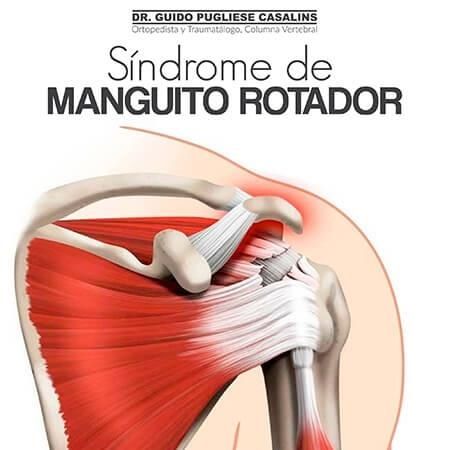

Ortopedista y traumatólogoOrtopedista de columna vertebralEscoliosis

Las especialidades de Dr. Guido Pugliese Casalins son: Ortopedista y traumatólogo, Ortopedista de columna vertebral, Escoliosis.